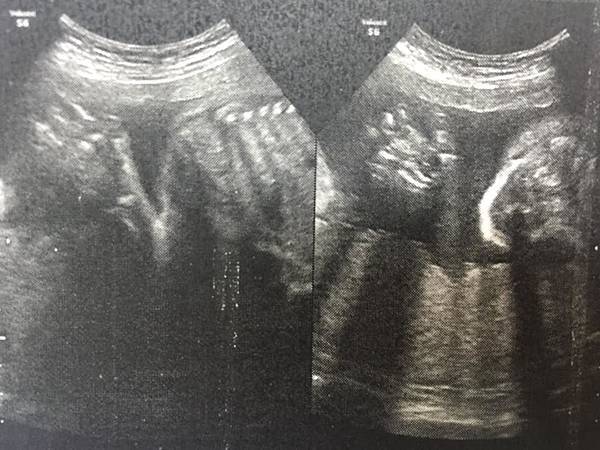

這是之前我因腎盂腎炎住院期間 懷孕24周在馬偕照的,是不是從媽媽角度看起來有點難懂 哈~